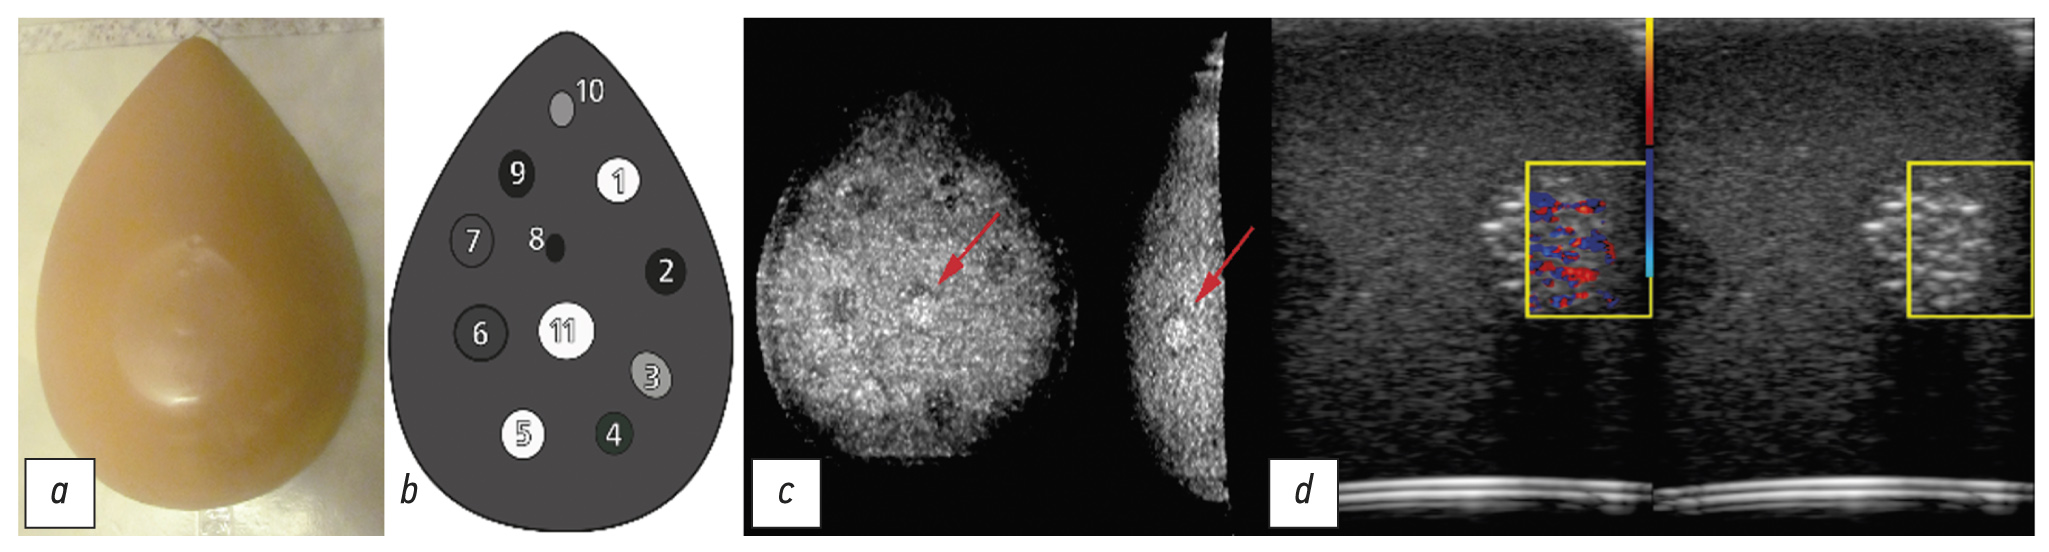

- A set of examinations of elastographic breast Blue Phantom with the data that have been taken with a linear transducer at 5, 9, and 17 pulses in sequence for a pulse repetition frequency of 150 Hz and at 17 pulses and repetition frequencies of 300 Hz, 500 Hz, 750 Hz, and 1 kHz.

Fig. 10. Phantom of the mammary gland Blue Phantom: a - appearance; b - connection diagram; c - sections of a computed tomogram (the arrow indicates the area under study); d - sonogram.

The phantom (photo and scheme shown in Fig. 10 a, b) contains inclusions that simulate micro calcifications, which are indicated by an arrow in a slice of the computer tomogram in Fig. 10c. On these inclusions, a twinkling artifact was observed at a low pulse repetition frequency in the CFM mode (Fig. 10d). With increasing frequency, the intensity of the artifact decreased until it completely disappeared at frequencies above 1 kHz.